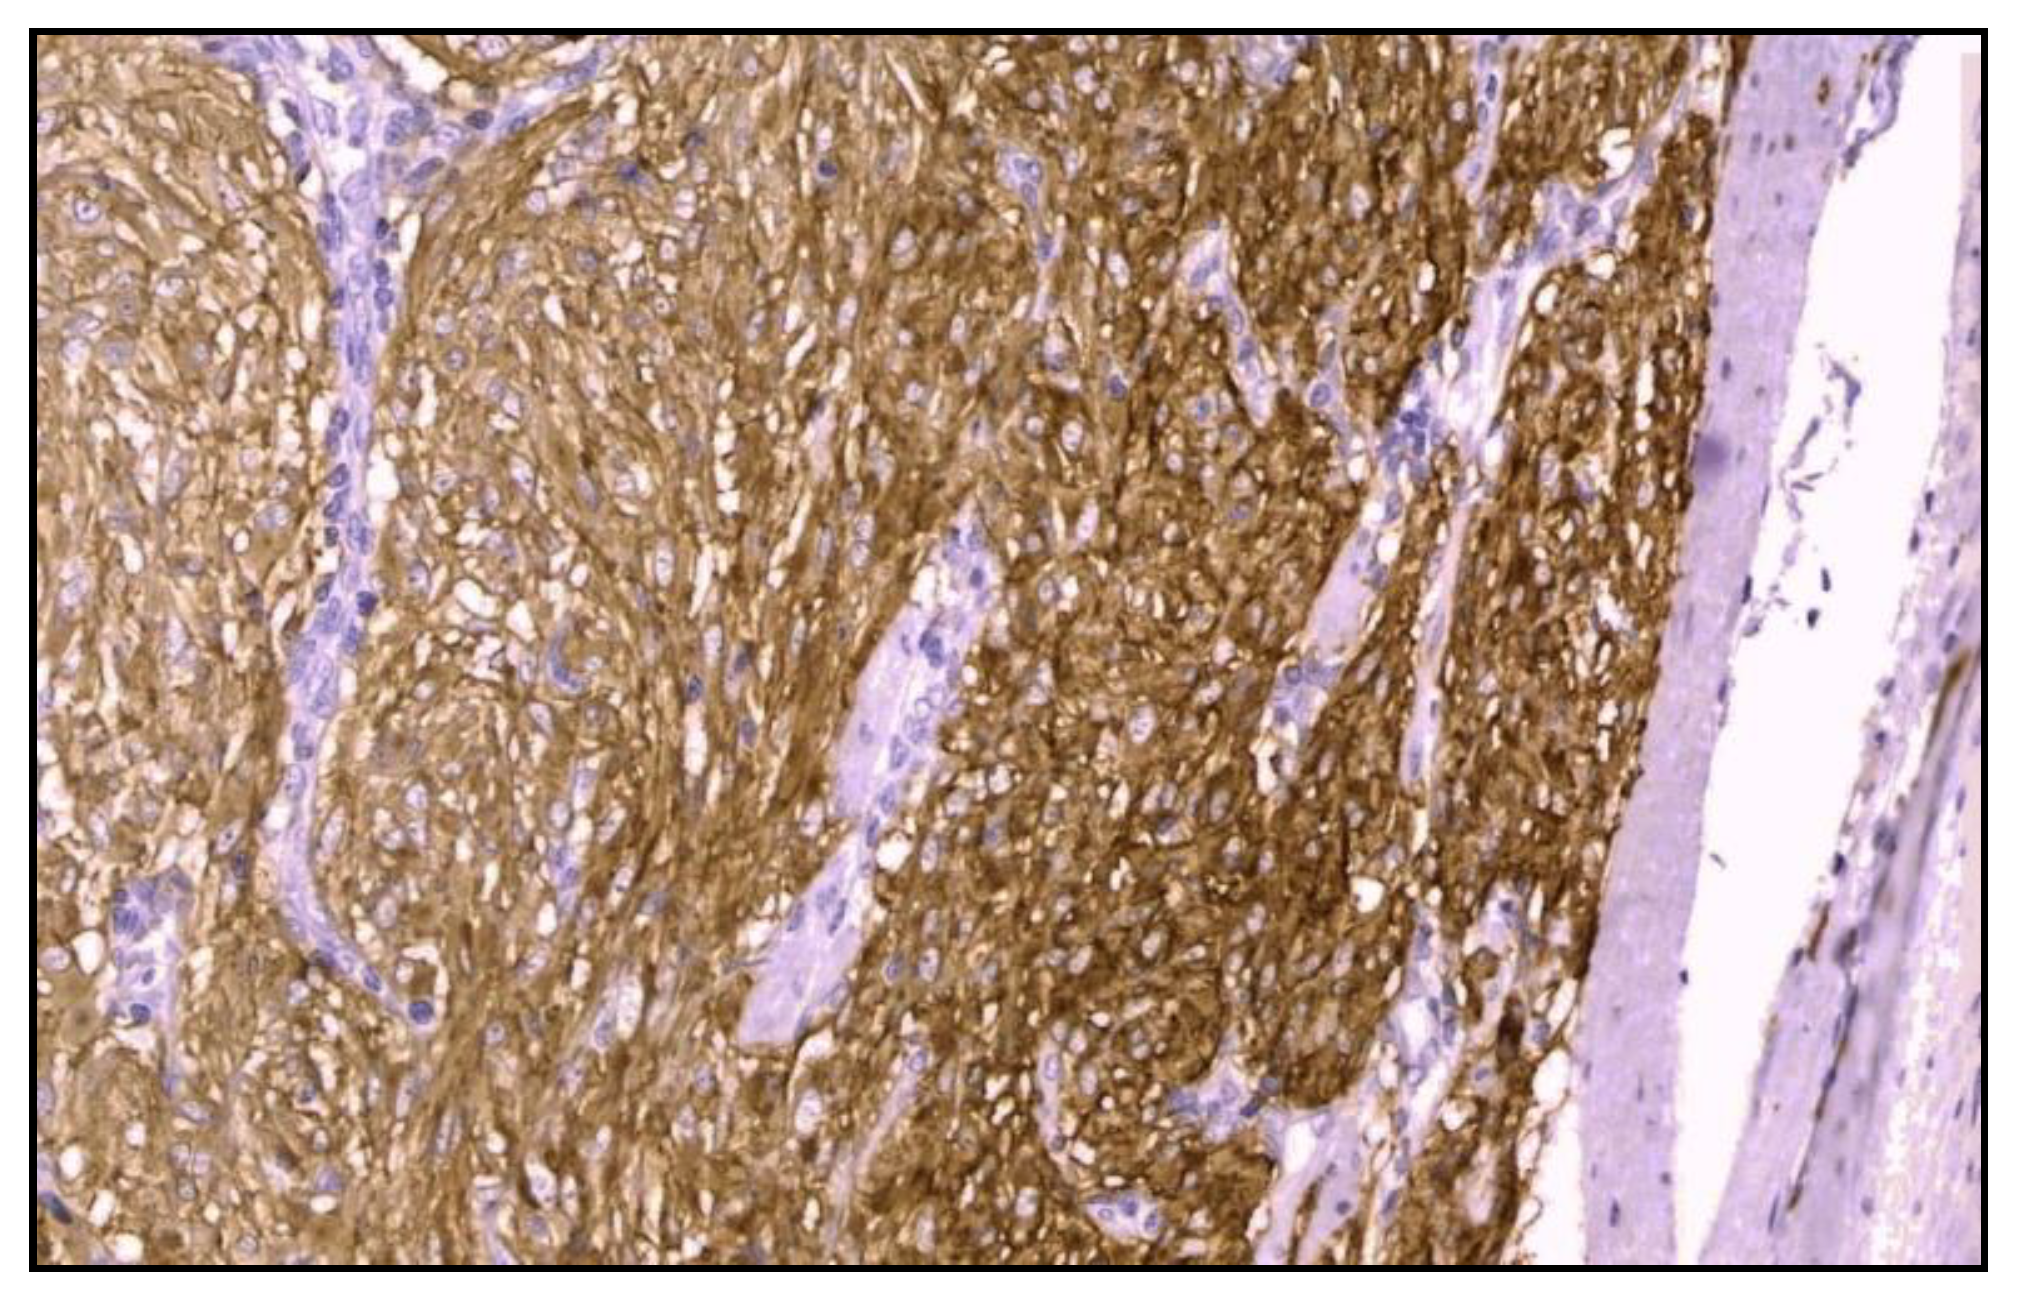

Immunohistochemistry was positive for CD117/c-kit and CD34 immunomarkers (Figure 6) and negative for desmin, vimentin, muscle-specificactin, smooth muscle actin, S-100protein and neuron-specific enolase.

Figure 6. Microscopic finding immunohistochemistry exhibiting a strong positive for CD117 (CD117 staining; optical magnification of 40x).